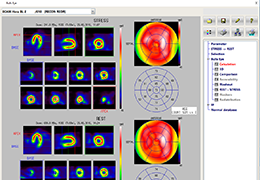

Performs 3D reconstruction and volume rendering.

Multi-planar slicing.

Side-by-side comparative assessment for pre- and post-operative scans.